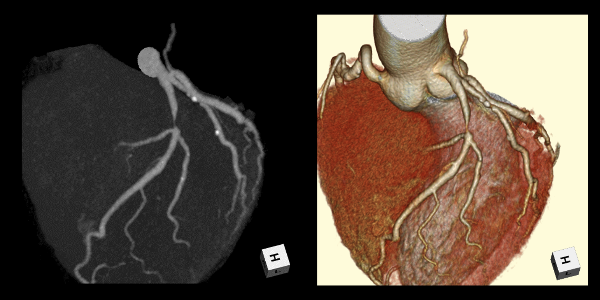

心臓CT:Coronary CT

心臓を撮影し、冠動脈画像を描出する検査です。検査時間はおよそ30分です。

心臓CT画像